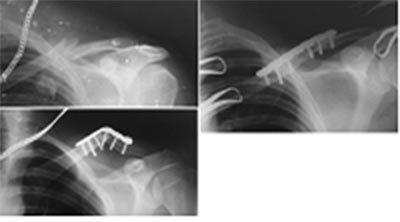

Больной Т.24 года. Косой перелом левой ключицы.Операция (31.12.2014): Остеосинтез левой ключицы пластиной. 05.05.2015 (через 5 мес.) Во время поездки на велосипеде получил боковой удар в область плеча, вследствие падения. Представлены рентгенограммы: до операции, после, после повторной травмы.Обязательно ли, вополнить костную пластику во время реостеосинтеза.

Вы имеете дело с несросшимся переломом ключицы. Из этого нужно исходить, планируя ревизионное вмешательство. Мне бы казалось уместным использование более длинной пластины, установленной по передне-нижней поверхности ключицы с костной пластикой

Если бы перелом сросся до падения, то, пациент, при достаточной энергии травмы, скорее, получил бы переимплантный перелом.

Снимки, к сожалению, не очень высокого качества. Но видно, что вершина деформации приходится на один из винтов. Так что, если предположить, что область первого перелома была между винтами, нынешний перелом вполне может быть новым. В любом случае показан остеосинтез. Конечно, более длинной пластиной. Какую поверхность выбрать для укладки пластины? Уже есть одна скомпрометированная поверхность. Ее все равно нужно снова открывать для удаления пластины. Стоит ли одновременно обнажать и другую поверхность? А костная пластика никогда не помешает. Лишние 15 минут операции и пара-тройка дней умеренной болезненности стоят того, чтобы быть уверенным в последующем сращении.

согласен с сергеем, пластина длиннее. Мне кажется лучше использовать прежний доступ, если зайти снизу - потеряем остатки кровоснабжения и костная платика чипсами - обязательно для стимуляции остеогенеза.